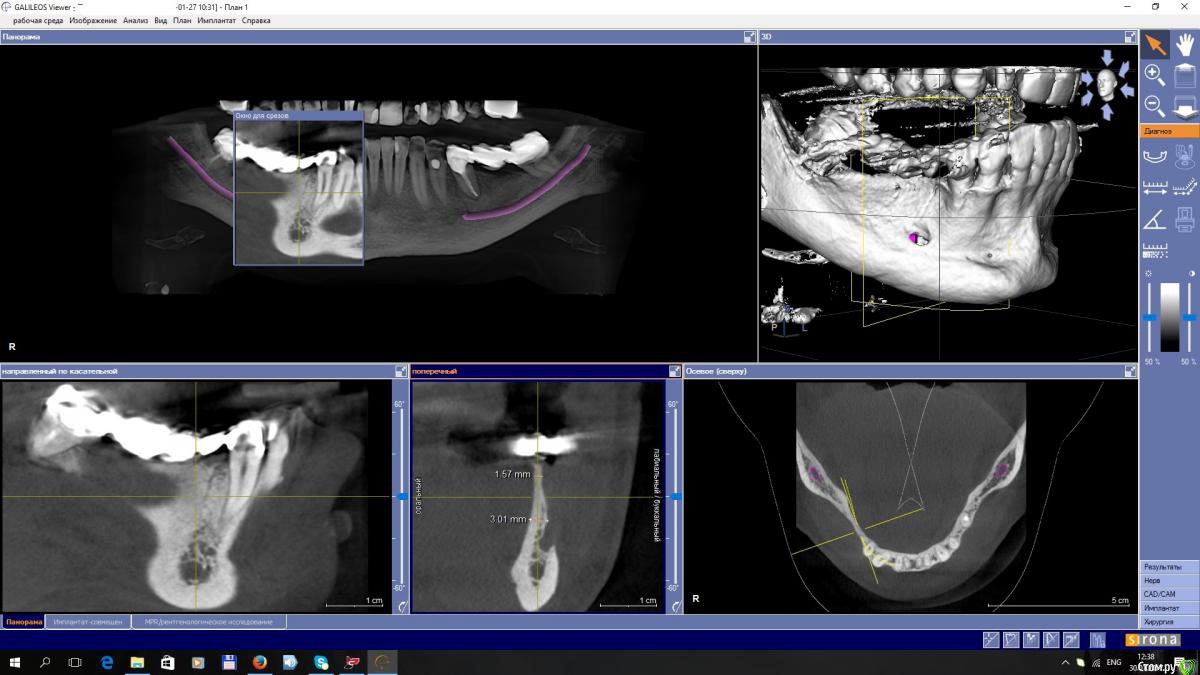

EEcho Опубликовано 30 января, 2017 Автор Поделиться Опубликовано 30 января, 2017 покажите срезы дальше(дистальнее) может целесообразно провести аугментацию дистально, возможно там ситуация получше... и сделать медиальную консоль на 5ый зуб.Срезы в области 45, 46, 47,48, Ссылка на комментарий

kamranchick Опубликовано 28 января, 2017 Поделиться Опубликовано 28 января, 2017 Уважаемые коллеги!Прошу совета!? Как увеличить объём, каким методом? Я в затруднении. За ранее большое спасибо!покажите срезы дальше(дистальнее) может целесообразно провести аугментацию дистально, возможно там ситуация получше... и сделать медиальную консоль на 5ый зуб. 1 Ссылка на комментарий